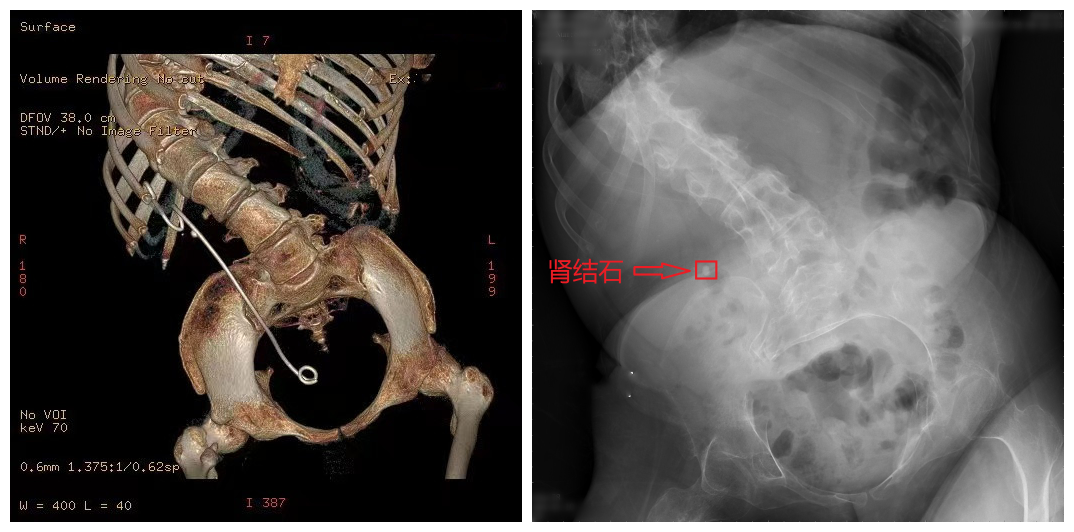

图为患者影像资料

吴磊来到北京清华长庚医院泌尿外科的门诊时,肖博副主任医师还以为眼前人是个孩子。因幼时患上神经源性肌萎缩病,导致脊柱、胸廓发育畸形,24岁的吴磊身高只有1米2,体重60斤,这也是导致他一直未能接受结石手术治疗的原因——麻醉、手术路径都是挑战。“看到他的情况,就特别想帮他解决肾结石的问题。”肖博说。